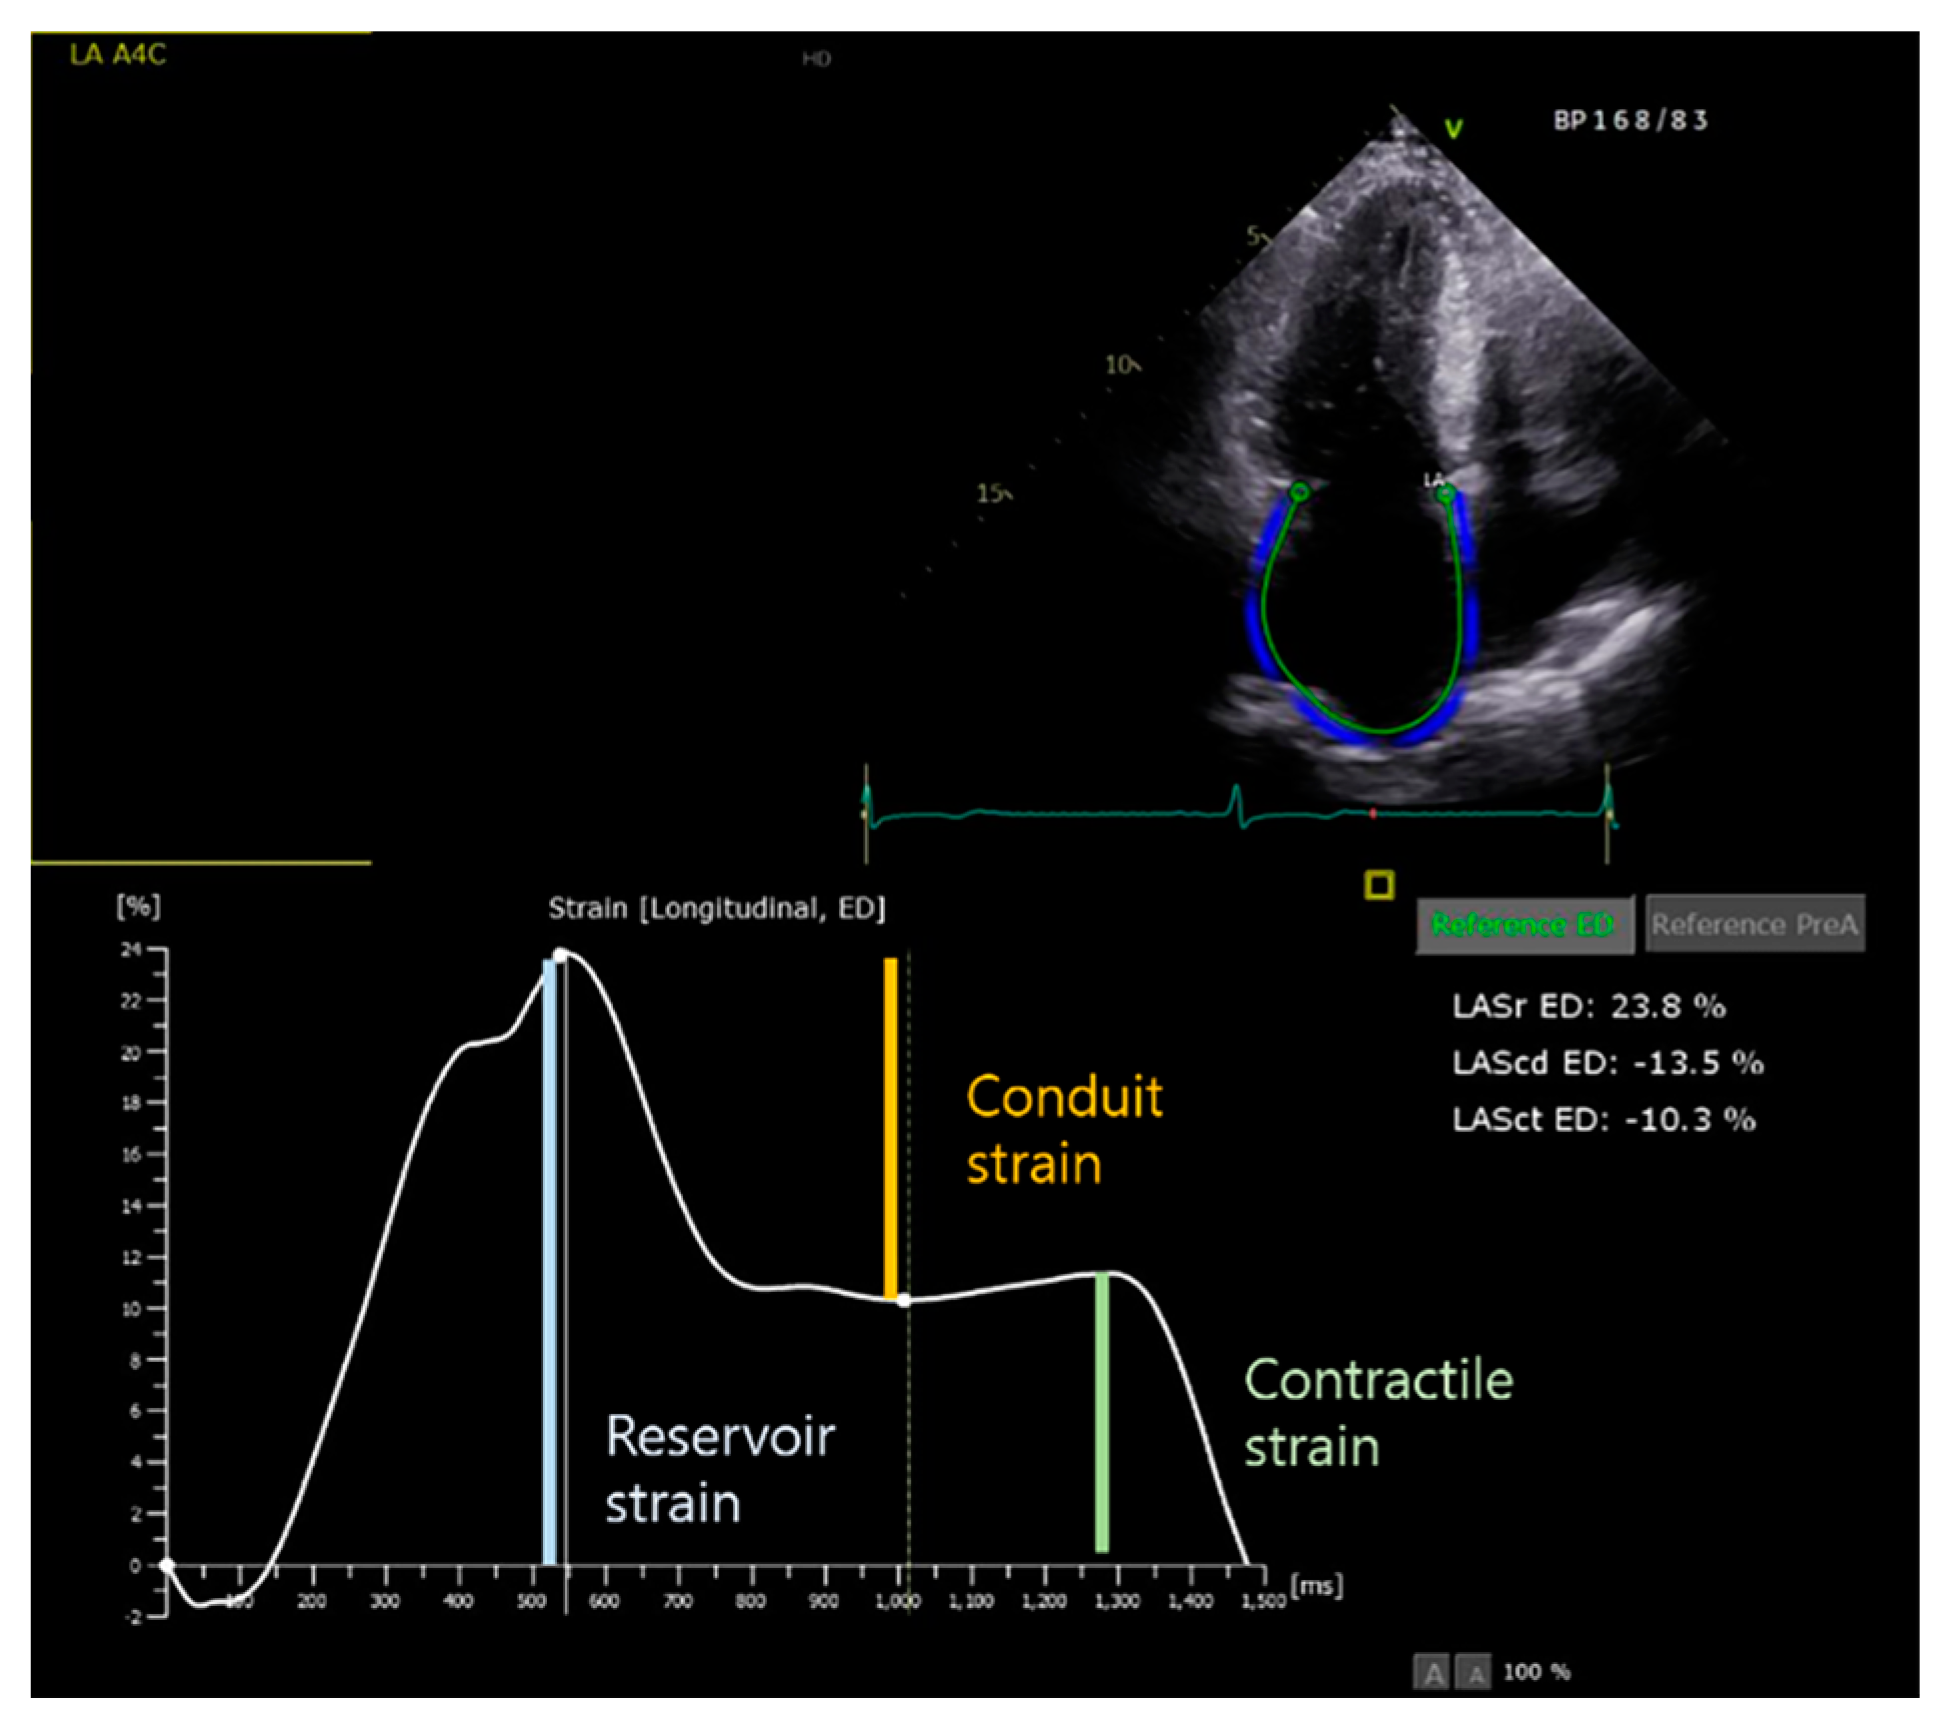

- Rosca, M.; Lancellotti, P.; Popescu, B.A.; Piérard, L.A. Left atrial function: Pathophysiology, echocardiographic assessment, and clinical applications. Heart 2011, 97, 1982–1989. [Google Scholar] [CrossRef] [PubMed]

- Ji, M.; He, L.; Gao, L.; Lin, Y.; Xie, M.; Li, Y. Assessment of Left Atrial Structure and Function by Echocardiography in Atrial Fibrillation. Diagnostics 2022, 12, 1898. [Google Scholar] [CrossRef] [PubMed]

- Nielsen, A.B.; Skaarup, K.G.; Hauser, R.; Johansen, N.D.; Lassen, M.C.H.; Jensen, G.B.; Schnohr, P.; Møgelvang, R.; Biering-Sørensen, T. Normal values and reference ranges for left atrial strain by speckle-tracking echocardiography: The Copenhagen City Heart Study. Eur. Heart J. Cardiovasc. Imaging 2021, 23, 42–51. [Google Scholar] [CrossRef] [PubMed]

- Cameli, M.; Caputo, M.; Mondillo, S.; Ballo, P.; Palmerini, E.; Lisi, M.; Marino, E.; Galderisi, M. Feasibility and reference values of left atrial longitudinal strain imaging by two-dimensional speckle tracking. Cardiovasc. Ultrasound 2009, 7, 6. [Google Scholar] [CrossRef]